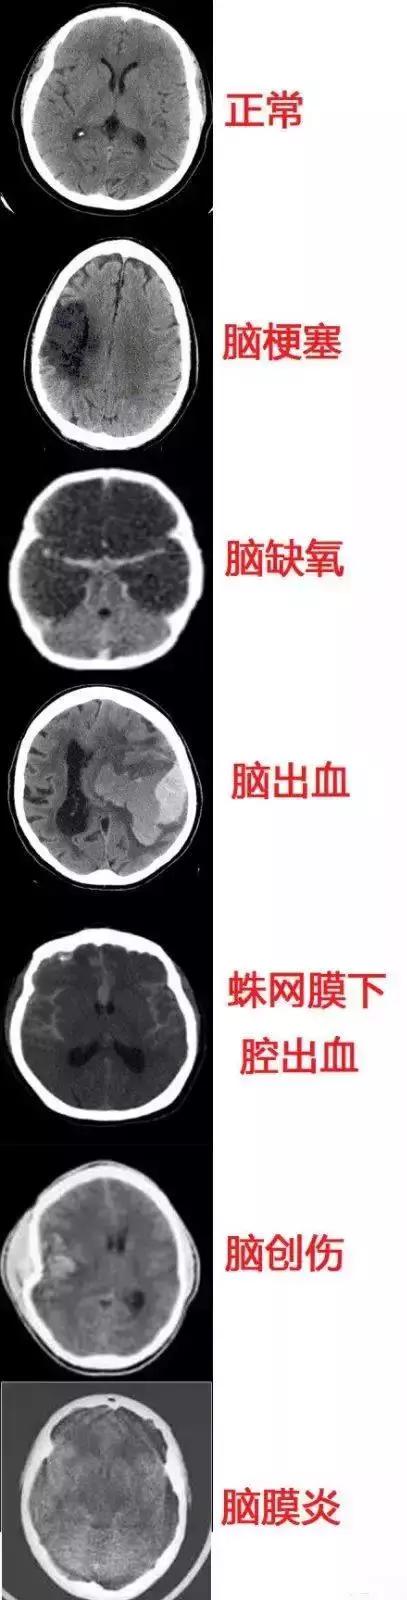

几种常见致死性脑病的CT表现

脑损伤